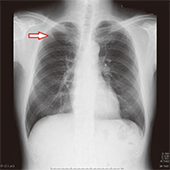

胸部X線では5mmの淡い結節影がありますが、画像を拡大しても肋骨に隠れており非常に見つけにくい状態です。同じ部位を胸部CTで撮影すると明らかに白く明瞭にがんが描出されています。

X線

X線拡大画像